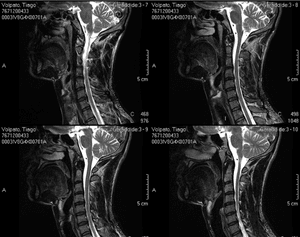

Olá, eu sou o Tiago. Há cerca de 1 ano e meio fui diagnosticado com Radiculopatia Cervical, que irradiou para ombros e braços, causando dor crônica. Já passei 4 meses na cama sem conseguir me movimentar. Perdi a força e sensibilidade dos braços. Agora sigo com afastamento médico do trabalho para focar na recuperação com fisioterapia e medicação, que tem gerado um alto custo no meu tratamento. Em particular, devido ao meu trabalho, os médicos indicaram uma cadeira ergonômica que se ajusta à melhor posição para não afetar minha cervical e coluna lombar. No entanto, quando fui procurar, o valor da cadeira é muito alto. Por isso criei essa vakinha online para tentar arrecadar o dinheiro necessário e adquirir a cadeira.